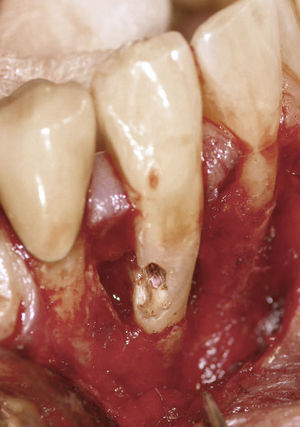

TratamientoSi se opta por tratar el diente, se lleva a cabo una endodoncia. Posteriormente se procede a la exposición quirúrgica del defecto y se repara con un material adecuado. La determinación de la longitud de trabajo por medio de una conductometría electrónica es complicada debido a que el tejido de granulación que ha penetrado en el defecto provoca una señal anticipada. Para la preparación conviene utilizar instrumentos manuales, dado que proporcionan una mejor sensación táctil para salvar la laguna de reabsorción. Se recomienda también el uso de una medicación intraconducto con hidróxido de calcio. En una segunda sesión se obtura con gutapercha termoplastificada la porción apical del conducto radicular. Después de la exposición quirúrgica del defecto de reabsorción se lleva a cabo el acabado de los márgenes (fig. 7).

En el momento de elegir el material de obturación conviene tener en cuenta diversos aspectos. El cemento de reparación MTA muestra una compatibilidad óptima con los tejidos y es muy resistente a la humedad, pero su manipulación es difícil en manos inexpertas sobre todo si los defectos son de gran tamaño17,18 (fig. 8). Si después del tratamiento el defecto obturado va a quedar expuesto al medio oral, se debería optar por un cemento de tipo IRM (Dentsply DeTrey, Konstanz), un cemento de vidrio ionómero o un composite. El composite exige mantener el campo de trabajo totalmente seco y se considera el material idóneo para defectos próximos a la zona marginal.